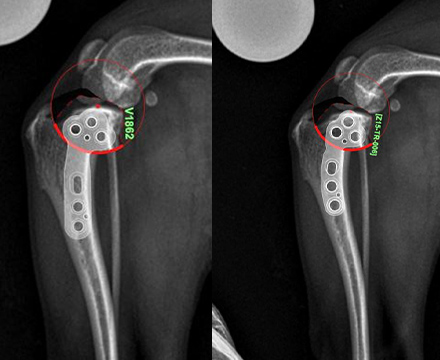

슬개골탈구 3기 + 십자인대질환

- modified TPLO with jeil TPLO 1.5 modified plate(6 holes)

- 4.3kg, 치와와

특수하게 휘어진 Jeil medical 1.5 modified TPLO plate를 사용하여

소형견 환자도 안정적으로 슬개골탈구와 십자인대를 동시에 교정할 수 있습니다.

슬개골탈구 3기 + 십자인대질환

- modified TPLO with jeil TPLO 1.5 modified plate (6 holes)

- 4살 3.5kg, 말티푸

슬개골탈구 3기와 십자인대질환에 대해 modified TPLO 진행하였습니다.

Modified TPLO 전용 특수하게 휘어진 플레이트를 사용하였습니다.

환자의 무릎의 병발 질환이 있을 경우

수술 방법을 일반적인 경우와 다르게 하는 등, 환자 맞춤 수술이 중요합니다.